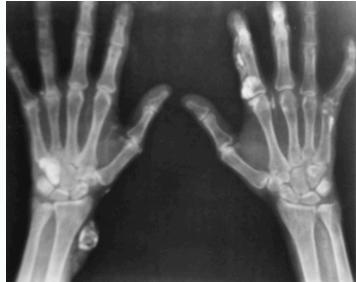

- Sub-periosteal resorption: middle phalanges, tibial shaft

- In hand, sub-periosteal bone resorption .This change usually happen in the middle phalanges, radial aspect in the 2nd or 3rd finger.

- Terminal tuft erosion.

Sub-periosteal bone resorption

- Most useful sign

- Virtually Diagnostic

- Location

Subperiosteal bone resorption (straight arrow), resorption of the tip of the terminal phalanx and the altered bone architecture. Arterial calcification is also present (curved arrow).